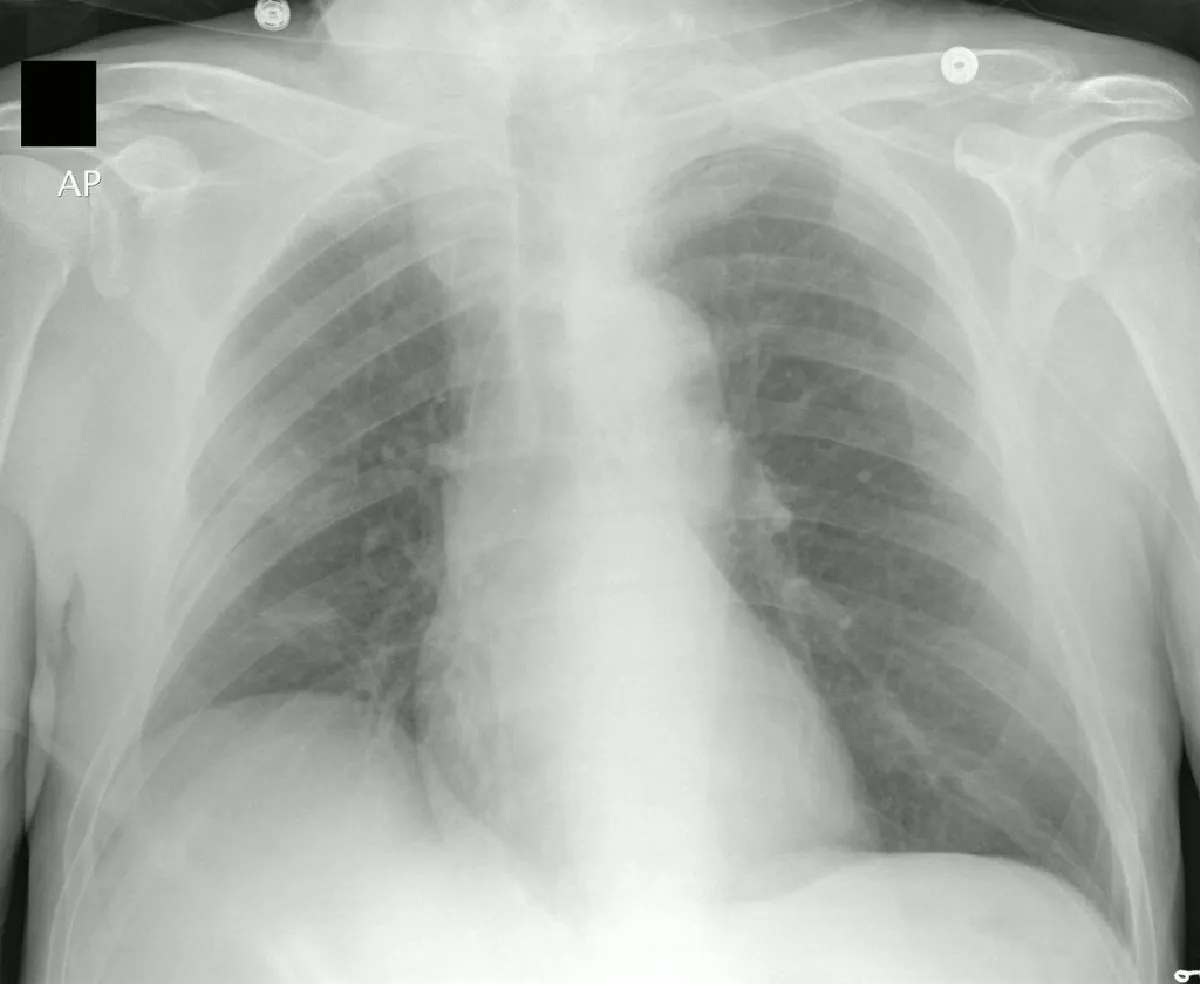

Only practitioners with advanced specialized training can insert CV access catheters. Special equipment needed includes a central line kit (Figure 13.18). Central line kits are sterile packages that include lidocaine, a syringe and needle to administer local anesthetic, syringe and introducer needle, scalpel, guidewire, tissue dilator, sterile dressing, suture and needle, and central line catheter. In addition, you will need a sterile gown, cap, gloves, sterile gauze, sterile saline, face mask, and chlorhexidine (or other antiseptic solution approved by the agency) when placing the central line. Nurses who are not certified to insert central lines can assist the practitioner by gathering the supplies needed to insert the line and assisting during the procedure. Ultrasound may be used to visualize the veins prior to beginning the procedure and to guide the central line placement. Once the central line is in place, a chest x-ray will verify correct placement of the central line prior to the line being used, if it was placed in the superior vena cava (Figure 13.19).

An X-ray image of a human chest with the tip of PICC line visible.

Figure 13.19 A chest x-ray confirms correct placement of the central line in the superior vena cava before use. (credit: “PICC line-correct position.jpg” by "Octavio L"/Wikimedia Commons, CC BY 2.5)